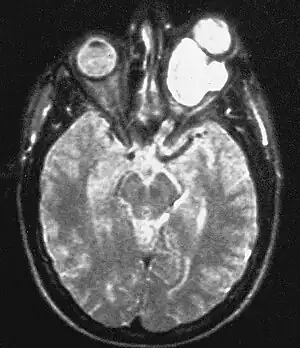

| Magnetic resonance image of a large retrobulbar optic nerve tumor causing massive proptosis | |

Optic nerve gliomas are diagnosed using magnetic resonance imaging (MRI) and CT scans.[6] The tumor adopts a fusiform appearance, appearing wider in the middle and tapered at the ends.[6] Enlargement of the optic nerve along with a downward kink in the mid-orbit is usually observed.[6] While CT scans allow for optic nerve evaluation, MRI allows for intracranial evaluation to observe if the tumor has extended to other regions such as the optic chiasm & hypothalamus.[7]